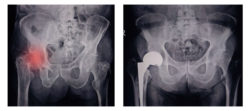

The Biomet hip replacement lawsuit was specifically filed over alleged defects linked to the Biomet M2A Magnum Hip System. This system was developed for a total hip joint replacement and used a metal on metal system.

Many hip replacement systems, according to the Biomet hip replacement lawsuit, use an acetabular liner that fits inside a cup. The Biomet M2A Magnum Hip system, however, does not and instead uses a metal femoral head that is directly placed into a one-piece metal acetabular cup. This then forces articulation from one metal component onto another with the full pressure and weight of the human body, which can cause significant pain and problems.

In 2009, the plaintiff says she received her hip replacement in Illinois and was implanted with a Biomet metal on metal M2A Magnum Hip System. In 2017, however, increasing pain in her right hip led the plaintiff to visit with an orthopedic surgeon.